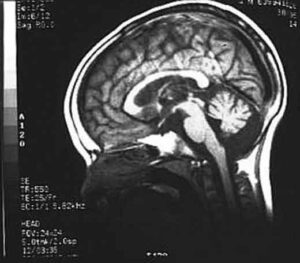

Identificato il difetto genetico responsabile di una particolare forma genetica di atassia, la SCA28. Il termine atassia deriva dal greco...